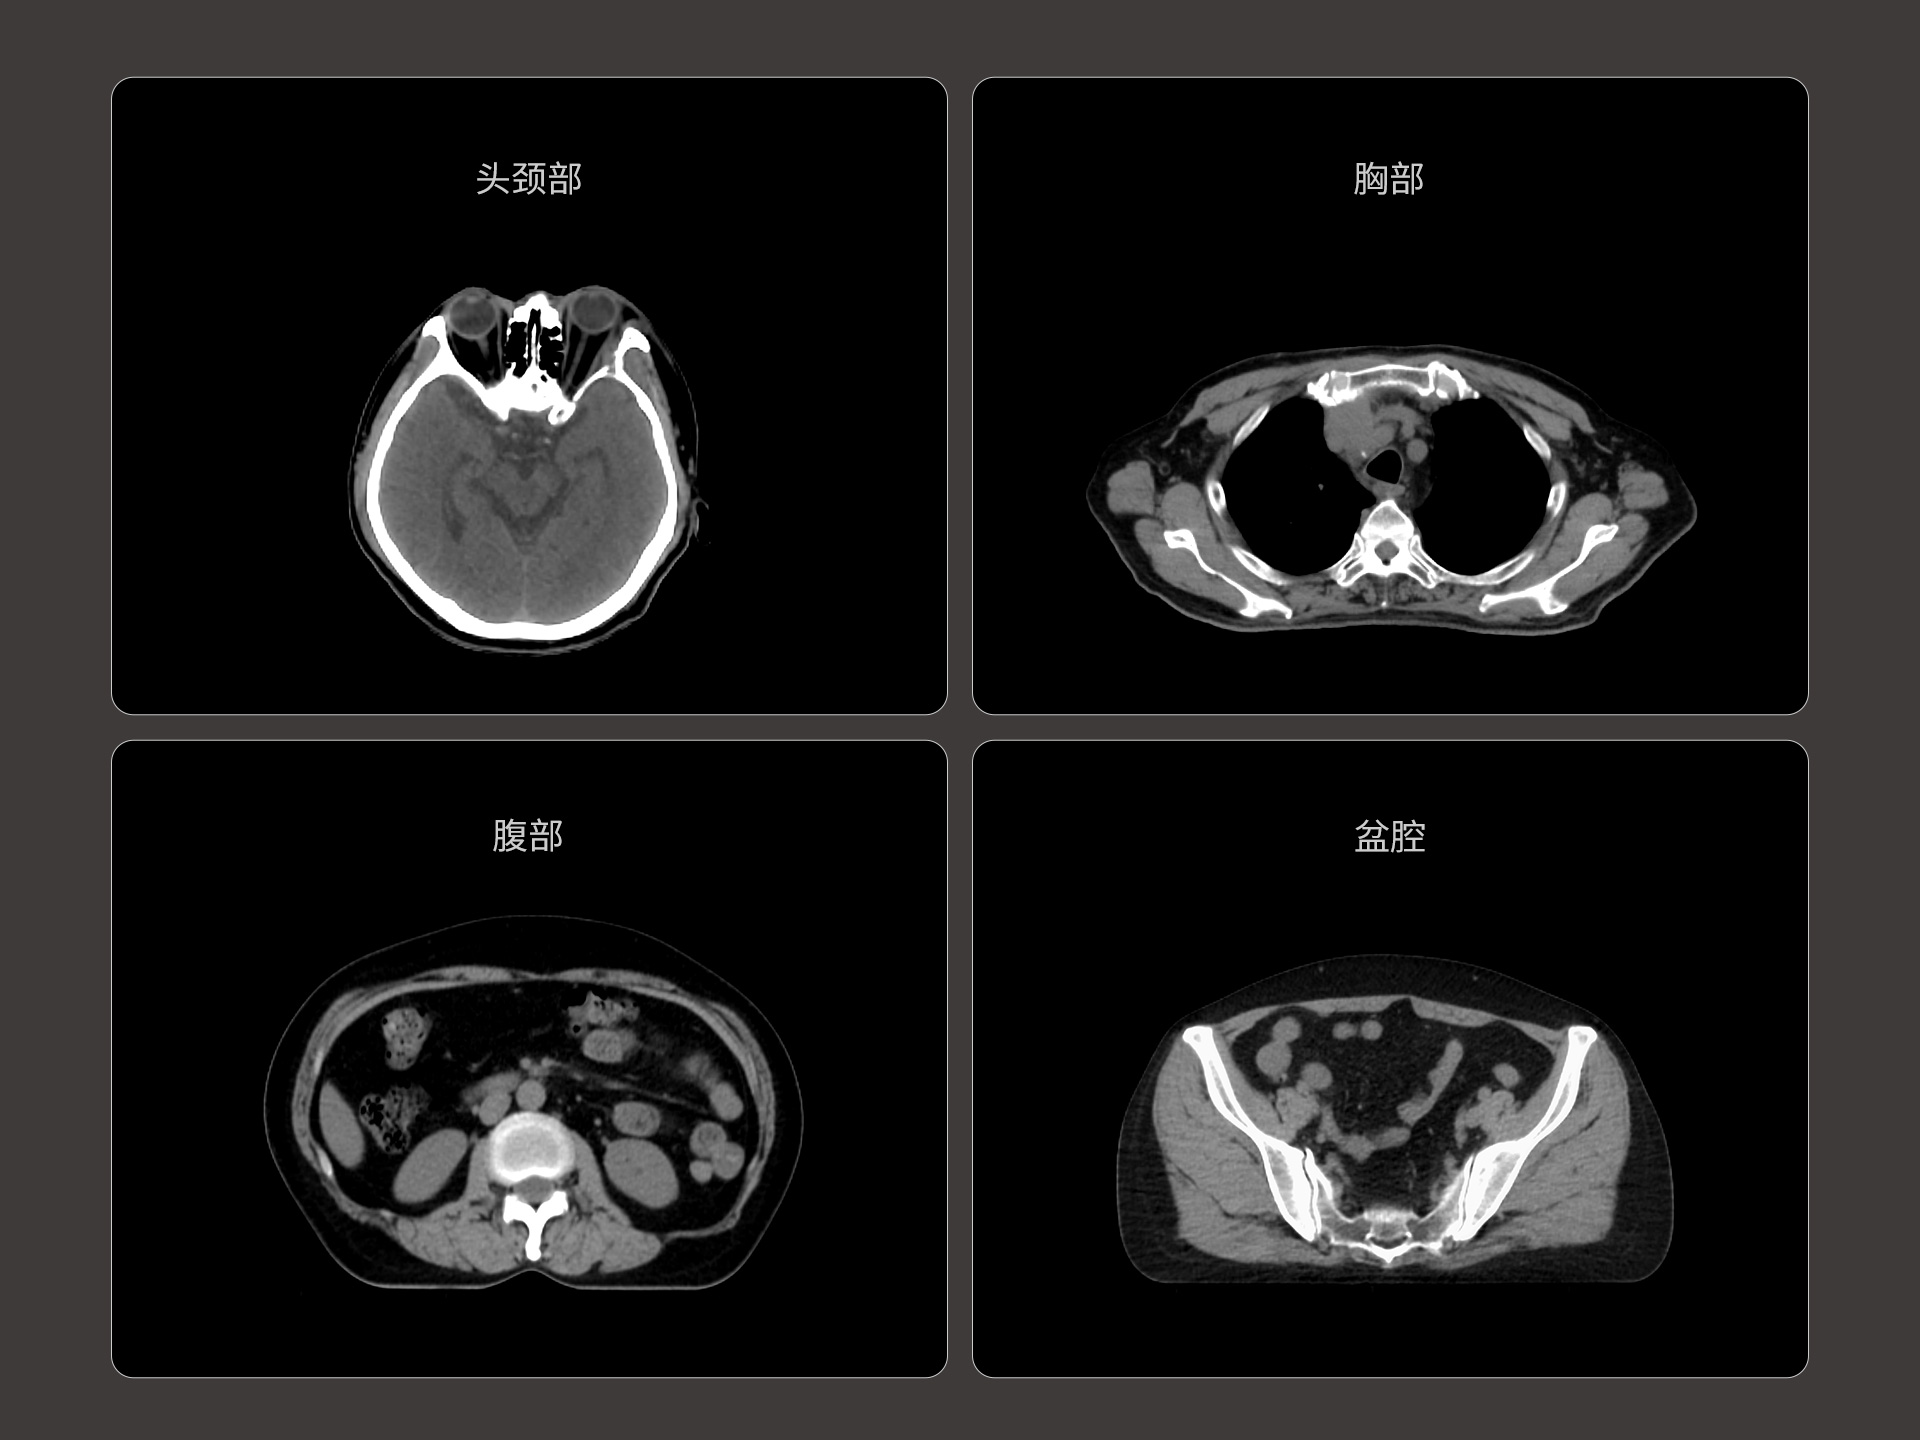

uLinac HalosTx®搭载新一代 87cm 大孔径诊断级CT图像引导系统,全能进阶,实现高清图像质量和全景视野的完美平衡,开辟全疗程 「影像感知」 ,为临床提供更自信、更全面的临床依据。

扇形束成像,极低散射,媲美CT-sim的影像品质

3mm @ 0.3% 高软组织对比度,0.55mm薄层扫描,精确鉴别肿瘤靶区边界

全疗程肿瘤变化感知,加速高清影像引导高水平普及

精准CT值,完美满足勾画、剂量计算要求

从数据源头提升图像质量,高清呈现细微变化,全面精进机载影像实力

提供传统 的CT 模拟机所一致的HU值精度(±10HU)

87cm CT影像孔径设计适配多种摆位姿势,兼顾不同体型患者

标准视野 63cm,避免扫描信息缺失

轴向视野 91cm,轻松实现长靶区扫描